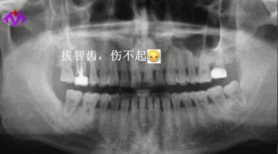

明明知道智齒就是口腔里的“定時(shí)炸彈”,極容易導(dǎo)致智齒冠周炎、損害鄰牙等問題,卻因?yàn)榕绿邸⑴侣闊?、想省錢,非得等到問題爆發(fā),才肯踏進(jìn)牙科的大門。

智齒長的位置不同,拔除的收費(fèi)也不一樣。